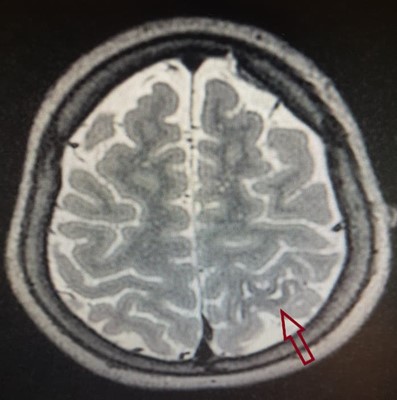

As lesões extra-hipocampais são todas aquelas esparsas pelo córtex cerebral, sendo de etiologia tumoral (geralmente tumores de baixo grau, menos agressivos, com crescimento lento) ou não tumoral, como displasias (malformações estruturais do cérebro). Muitas vezes o diagnóstico definitivo se faz após a cirurgia, por análise histopatológica.

Ressonância magnética de crânio, sequência T2, demonstra lesão displásica cortical